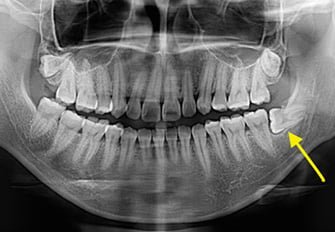

Are you in need of wisdom tooth removal in Damansara Heights? Look no further than iCare Dental Damansara Heights, your trusted partner in dental health. Our dedicated team of dental professionals possesses the knowledge and skills to perform wisdom tooth extractions with absolute precision and care.

No matter the complexity of your wisdom tooth problem, our team at iCare Dental Damansara Heights will provide comprehensive care, ensuring all necessary procedures are carried out with your comfort and safety in mind. Our seasoned professionals are selected based on their credentials and extensive experience in wisdom tooth extractions.

Wisdom tooth extraction requires specialized expertise to prevent complications, and it’s crucial that you get the right guidance and assistance. At iCare Dental Damansara Heights, we promise not just high-quality services, but also affordability. Once you’ve shared your needs with us, our team will ensure your dental health is managed effectively and efficiently